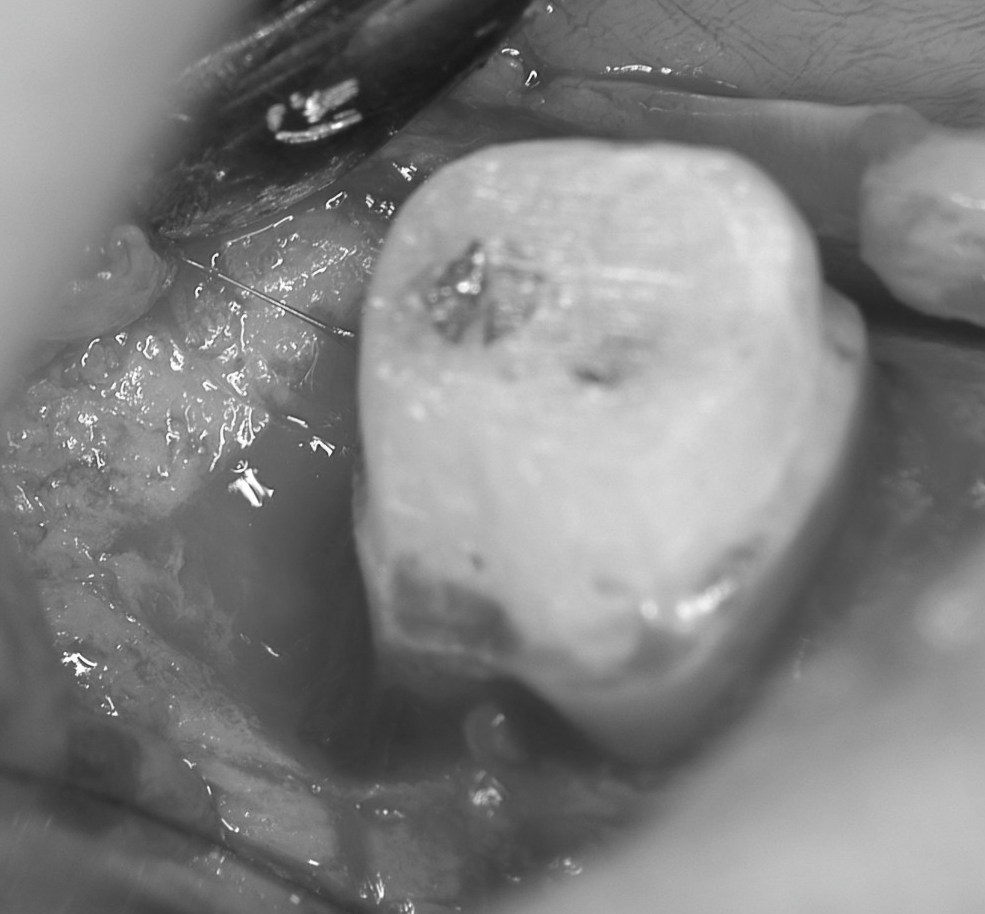

再生手術時の写真です。歯肉を切開・剥離した後に,骨が溶けて膿みが溜まっている部分を廓清し,歯石を除去しました。

骨面も根面もきれいにした後に,再生材料を骨欠損部に充填します。このケースでは自家骨移植を行いました。多くの場合,骨移植のみではなくエナメルマトリックスタンパク(エムドゲイン)やPDGFなどの成長因子を併用します。